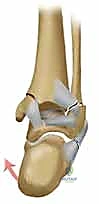

يصيب هذا الكسر عظمتي الكاحل الرئيسيتين: الشظية (التي تشكل الكعب الوحشي أو الخارجي) والظنبوب (الذي يشكل الكعب الإنسي أو الداخلي). يتطلب هذا النوع من الإصابات اهتماماً دقيقاً وتفصيلياً وتدخلاً جراحياً احترافياً لضمان الشفاء التام واستعادة وظيفة الكاحل بالكامل.

يتكون مفصل الكاحل من التقاء ثلاث عظام رئيسية:

1. عظمة الظنبوب (Tibia): وهي العظمة الأكبر في الساق، ونهايتها السفلية تشكل ما يُعرف بـ "الكعب الإنسي" (Medial Malleolus) وهو البروز العظمي الداخلي للكاحل.

2. عظمة الشظية (Fibula): وهي العظمة الأصغر في الساق، ونهايتها السفلية تشكل "الكعب الوحشي" (Lateral Malleolus) وهو البروز العظمي الخارجي.

3. عظمة الكاحل (Talus): وهي العظمة التي ترتكز عليها الساق وتعمل كحلقة وصل مع باقي عظام القدم.

عند كسر الكعبين (الداخلي والخارجي معاً)، يفقد الكاحل الحلقة التي تثبت عظمة الـ Talus في مكانها. هذا الانزياح، ولو كان بملليمترات قليلة، يؤدي إلى تغيير جذري في توزيع الضغط على غضروف الكاحل، مما قد يؤدي إلى خشونة مبكرة وتآكل في المفصل إذا لم يتم رده وتثبيته بدقة متناهية.